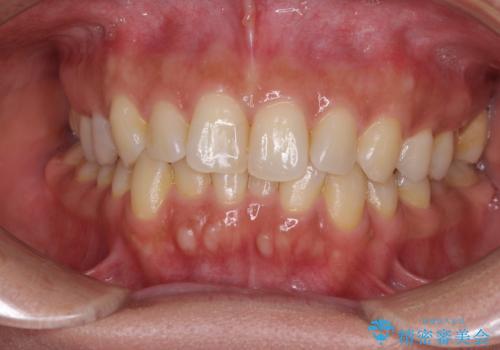

沖縄から飛行機で通院 インビザラインによる矯正治療

- 定期的に東京に来るので、沖縄から矯正治療で通院したいとのことで来院された患者様です。

歯列不正は軽度であったので、応急処置の少ないインビザラインにて矯正治療を行うこととしました。